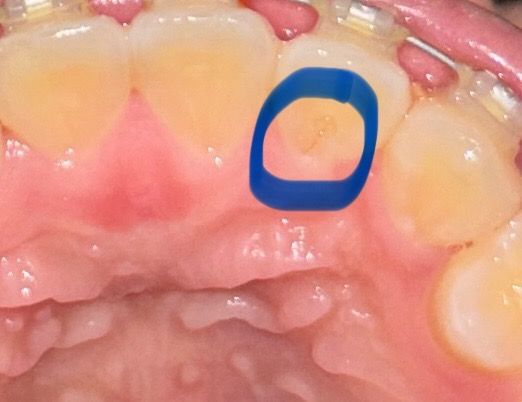

앞니 뒤쪽에 저런 선이 있는데 충치인가요 불과 2주전쯤 치과가서 충치이야기 할때는 앞니에 충치 잇다는 이야기는 못들엇는데.. 아프지듀 않습니다

네 충치입니다 충치가 잘 생기는 부위입니다 뒤쪽이라 주의깊게 보거나 특별히 충치가 있는지 점검해달라하지 않은 이상 못볼수도 있죠